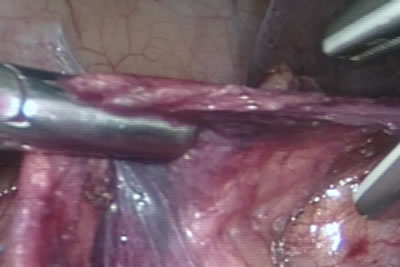

После рассечения брюшины восходящий отдел толстого кишечника

смещается медиально и обнажается правое забрюшинное пространство.

На снимке видна почка просвечивающаяся сквозь фасцию.